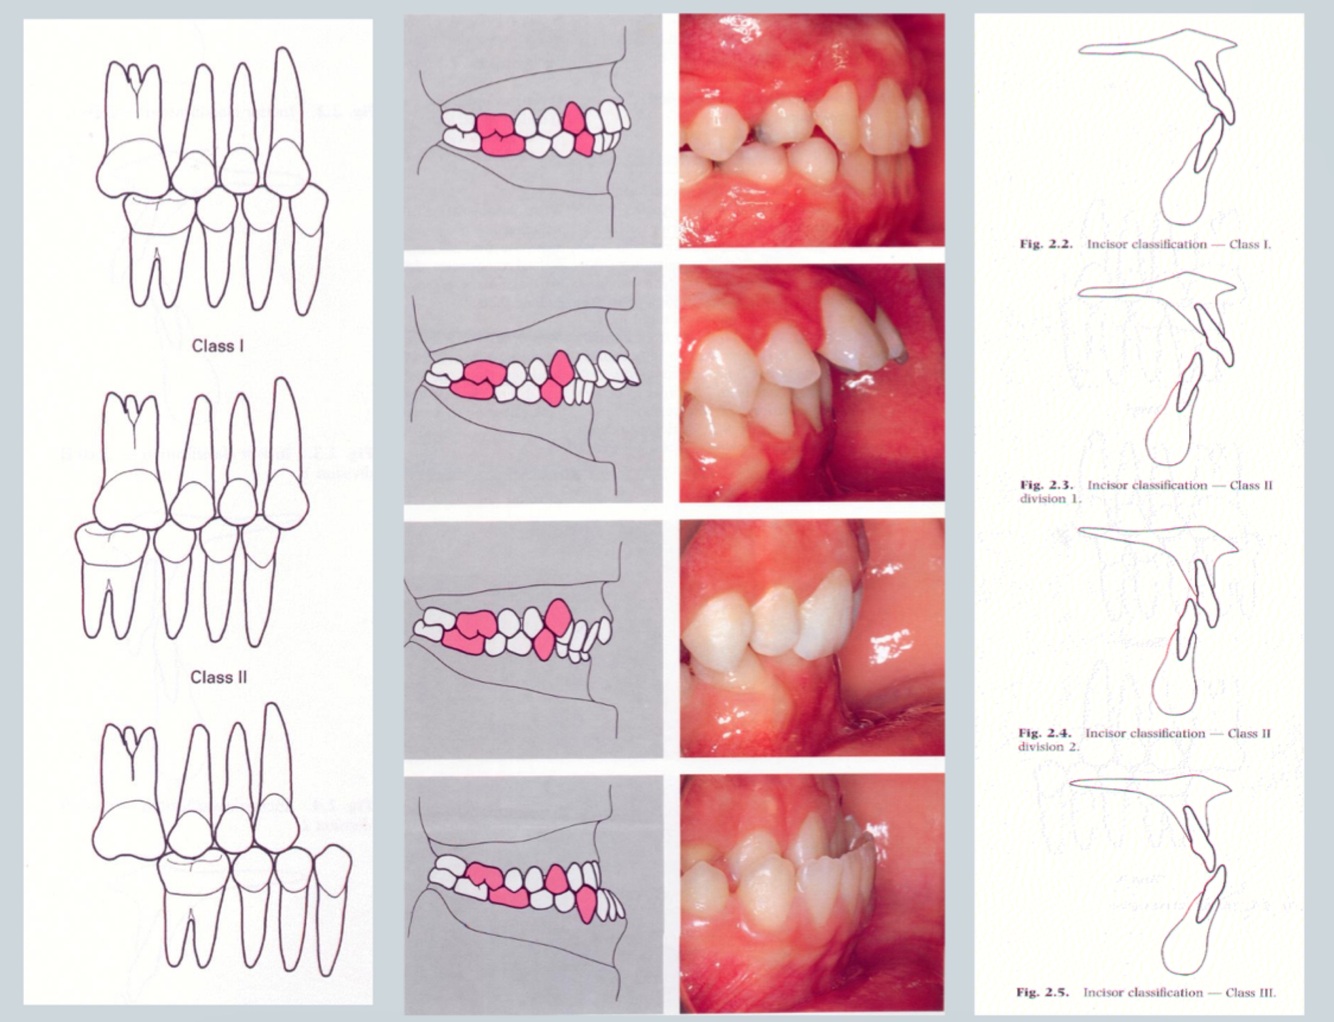

Identify class II div I

• incisors are proclined

• increase in overjet

• commonly these patients have class 2 molar relationship and class 2 canine relationship

Class II div I incisor relationship

British standards classification definition:

Upper incisors can be proclined or of normal inclination

• Tendency to incomplete bite

• Tendency to crossbite